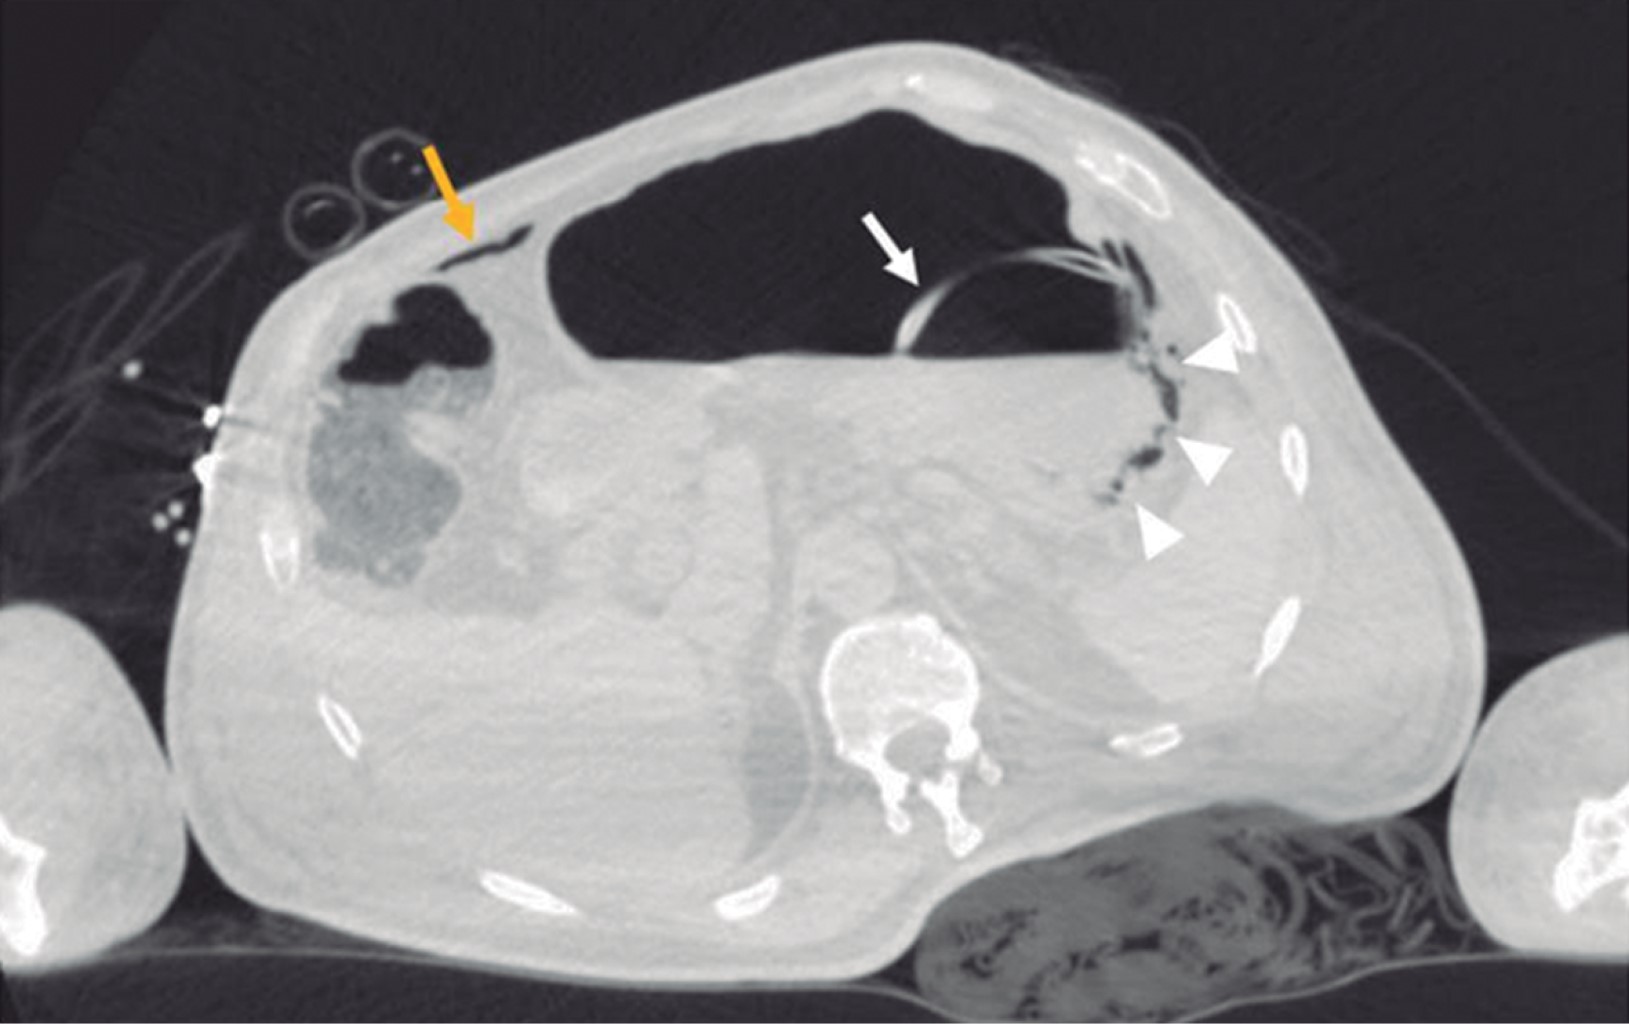

Paciente masculino de 69 años de edad con historia de diabetes mellitus tipo 2 en tratamiento con metformina y clorpropamida, hipertensión arterial en tratamiento con losartán y amlodipino. Se presenta al servicio de urgencias por mostrar cefalea, dolor torácico, tos, mialgias, artralgias y disnea de una semana de evolución. A su ingreso muestra frecuencia cardiaca 114 lpm, frecuencia respiratoria de 24 rpm, saturación de oxígeno de 80% sin apoyo de oxígeno suplementario, glucosa 587 mg/dl, leucocitos de 25,690 cel/mm3, neutrófilos 85%, linfocitos 1.2%, hemoglobina 16.3 g/dl, procalcitonina 3.78 ng/dl, gasometría arterial con pH 7.41, pCO2 21 mmHg, PO2 35 mmHg, HCO3 13 mmol/l, saturación de oxígeno 62%. Se realiza prueba rápida de antígeno para SARS-CoV-2 resultando positiva, tomografía axial computarizada (TAC) de tórax en la que se observan datos radiológicos sugestivos de infección por SARS-CoV-2 (Figura 1), se inicia manejo con oxígeno suplementario, bomba de infusión de insulina, carbapenémicos, antihipertensivos, dexametasona y profilaxis antitrombótica con enoxaparina. A las 48 horas de su ingreso continúa con choque séptico, se inician aminas vasopresoras, se realiza intubación orotraqueal y soporte con ventilación mecánica invasiva, se coloca sonda nasogástrica (SNG), la cual 24 horas posterior a su colocación reporta hematemesis acompañada de distensión abdominal, leucocitosis de 40,000 cel/mm3, se realiza TAC abdominopélvica simple, la cual revela neumatosis gástrica y neumoperitoneo (Figura 2), se efectúa laparotomía exploradora urgente encontrando necrosis de la curvatura mayor del estómago, se lleva a acabo gastrectomía vertical con engrapadora GIA cartuchos morados de 45 y 60 mm (Figura 3), se refuerza línea de grapeo con sutura continua prolene 00, se coloca sonda de yeyunostomía de alimentación a 60 cm del ángulo de Treitz y se dejan drenajes tipo Saratoga. A las 24 horas postoperatorias paciente reporta estabilidad hemodinámica y se suspenden aminas vasopresoras, se inicia nutrición enteral con dieta elemental. El quinto día postquirúrgico muestra adecuada tolerancia a dieta enteral por yeyunostomía, se realiza prueba con azul de metileno por SNG sin evidencia de fugas y descenso de leucocitos a 24,000 cel/mm3. Se recaba resultado de histopatología, el cual revela necrosis panmural asociada a trombosis arterial secundaria a microorganismos compatibles con Mucor sp., por lo que se inicia manejo con anfotericina B (Figuras 4 y 5). En el seguimiento muestra buena evolución, se realiza TAC abdominopélvica con contraste por SNG, la cual descarta fugas y colecciones intraabdominales y se corrobora integridad de la pared gástrica, se retiran drenajes y se da alta de cirugía general el día nueve postquirúrgico continuando manejo a cargo del servicio de medicina interna. Durante los siguientes días de hospitalización, el paciente presenta deterioro cardiovascular y pulmonar, se toma urocultivo, el cual evidencia crecimiento de Candida tropicalis, se realiza TAC de cráneo, tórax y abdominopélvica con contraste oral (Figuras 6 y 7), continúa sin evidencia de fugas a nivel abdominal, se descarta mucormicosis rinocerebral y pulmonar, se reporta probable neumonía bacteriana sobreañadida y neumopatía intersticial secundaria a COVID-19, persiste deterioro clínico y choque refractario, el paciente fallece a 29 días de su ingreso.

Figura 1